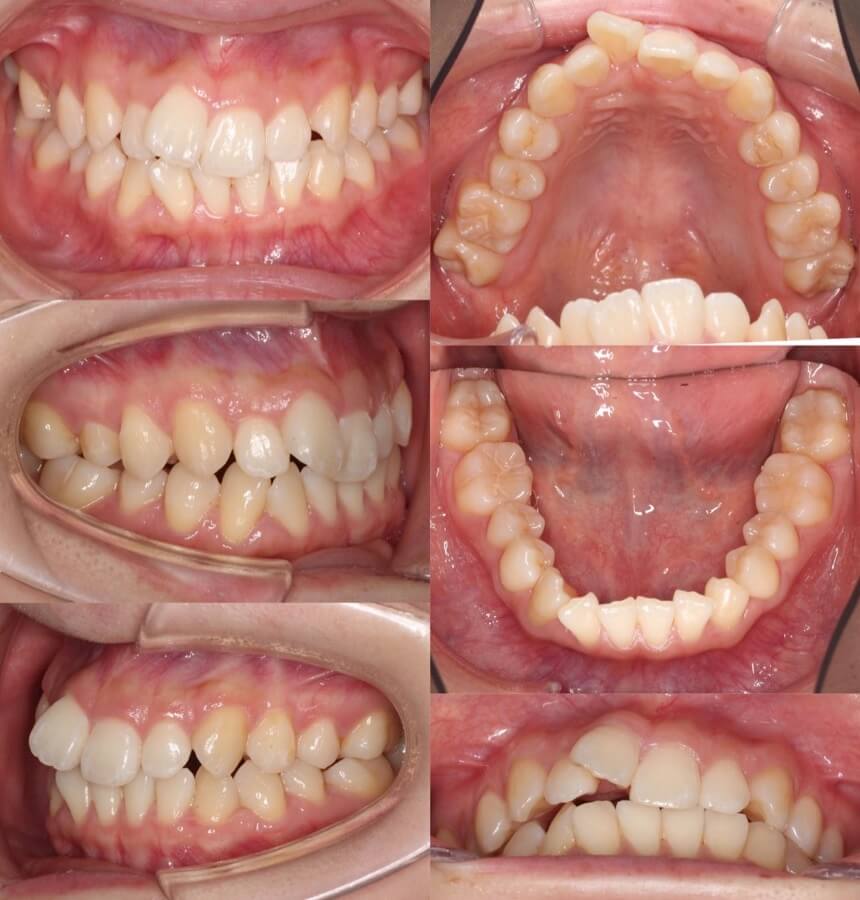

高校生女性・重度叢生・唇側装置・抜歯

歯並びのがたつきにより、上下の歯並びの正中線が大きくずれてしまっています。抜歯によるスペースを上手く利用して治療後はお顔の正中と上下の歯並びの正中を一致させました。

<症例概要> 難易度★★★★☆

主訴:八重歯

年齢・性別:高校生女性

住まい:千葉県八千代市

症状:八重歯・叢生・上下顎正中線の不一致

治療方針:抜歯空隙閉鎖・中等度固定

抜歯:上4番・下5番(計4本)

治療装置:唇側矯正装置

治療期間:2年9か月

リテーナー:上下フィックスタイプ+クリアタイプ

治療費用:990,000(税込)

代表的副作用:痛み・治療後の後戻り・歯根吸収・歯髄壊死・歯肉退縮